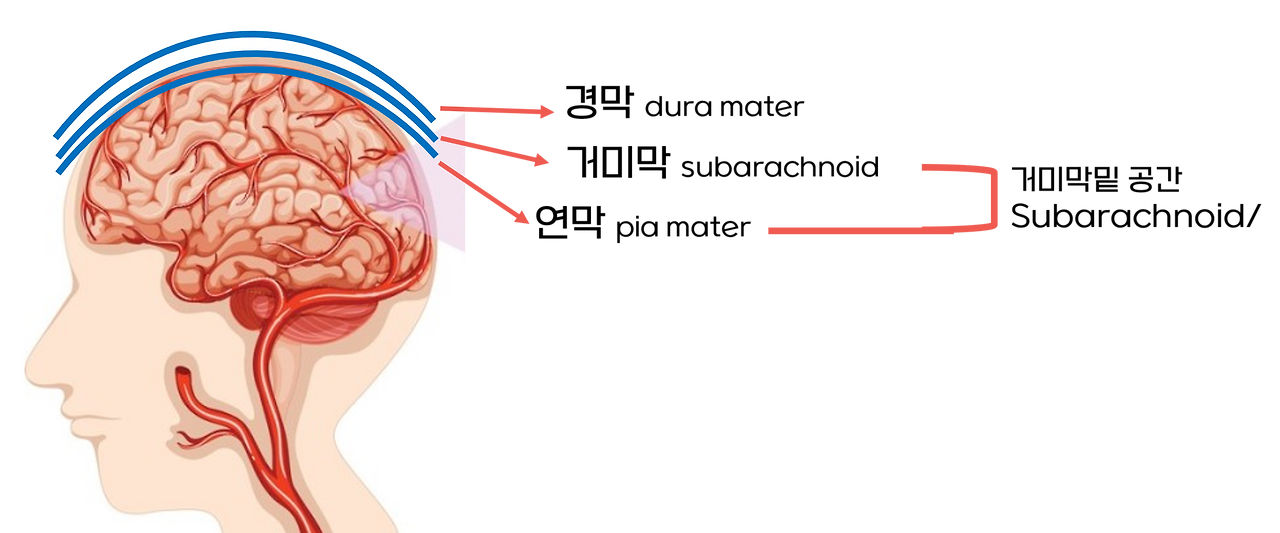

우리 뇌는

뇌 위에 3개의 막이 존재합니다.

그 막은 연막(연질막), 그 위에 거미막, 그 위 경막이다.

경막은 우리가 알고 있는 딱딱한 머리를 두드렸을 때, 딱딱한 뼈 아래 위치한다.

얼마나 중요한 부위인지, 이렇게 3개의 막으로 구성된 것 보면 이해할 수 있다.

그러니깐, 바로 거기 막밑 출혈이란 것은, 이 거미막과 연막 사이 공간을 말한다.

이 공간에 출혈이 생긴 것을 지주막밑 출혈, 또는 거미막밑 출혈이다.